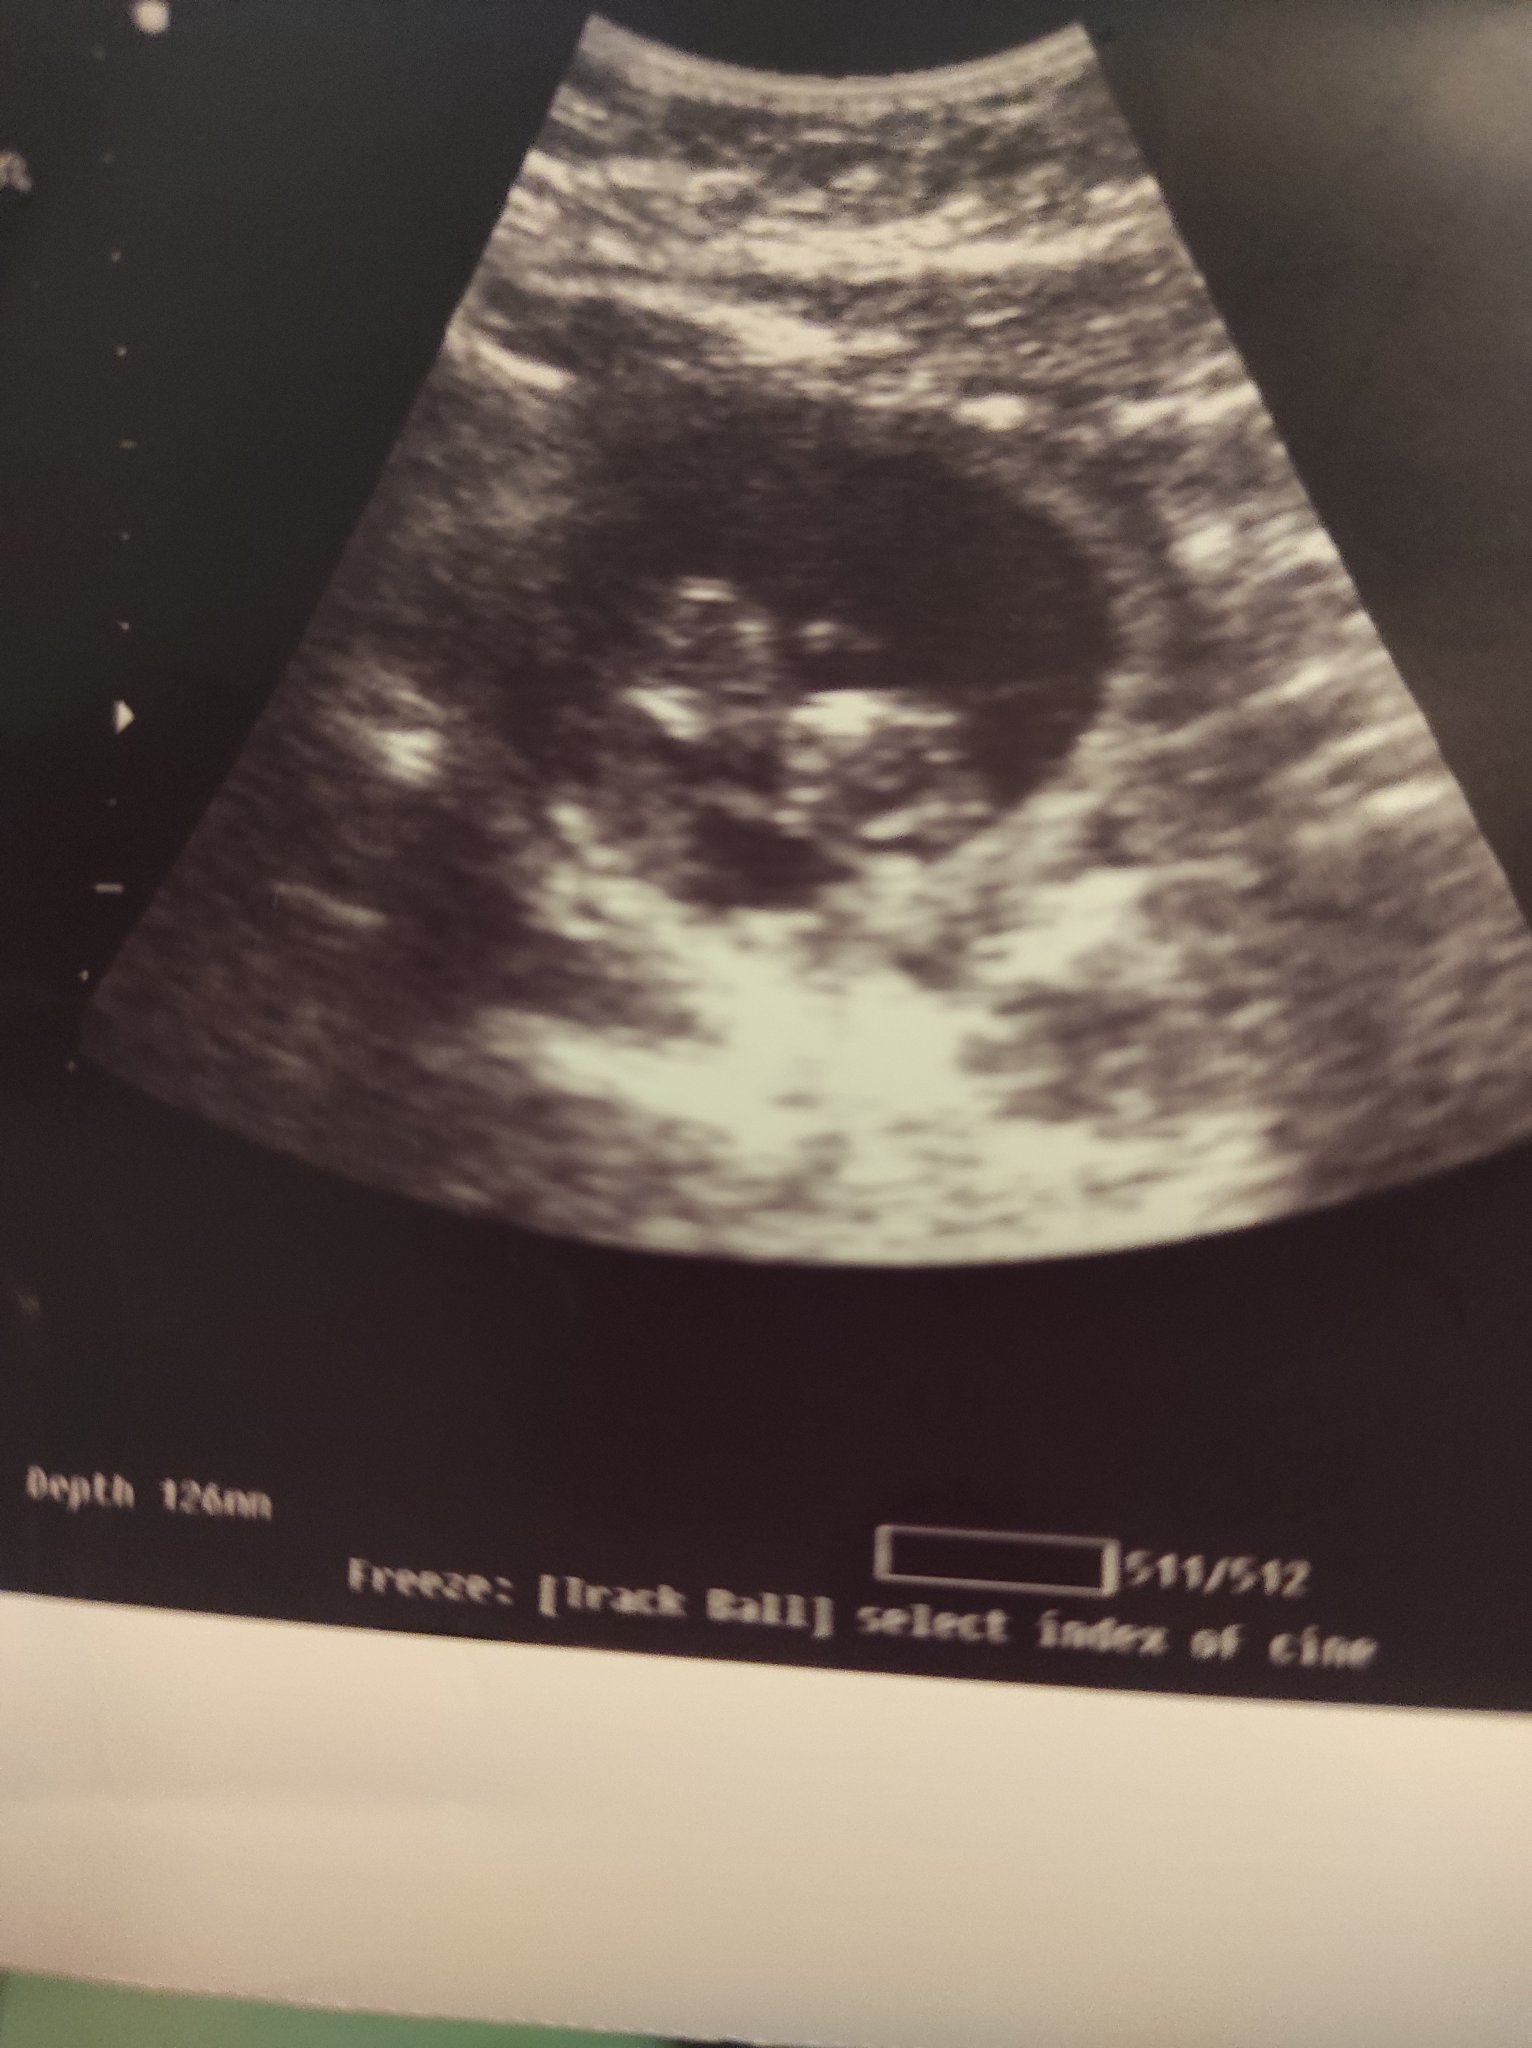

Много моля кажете мнение за снимката .

В 11 седм съм .

Гери,мнение за какво точно на снимката? Има си ембрион,но доста неясно се вижда.